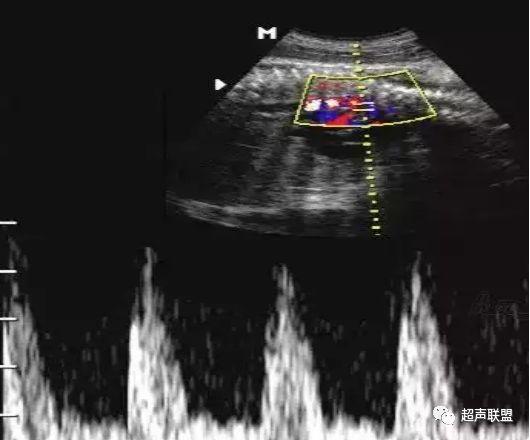

1 胎儿脐动脉测定

缺氧首先出现的变化是舒张末期血流降低,S/D值、RI值和PI值升高。当缺氧进入再分配晚期时,可逐渐出现舒张期血流减少、舒张期血流缺失。失代偿期出现脐动脉血液逆流,舒张期血流倒置。

图1 正常脐动脉血流频谱

图2 脐动脉舒张期血流消失或反向